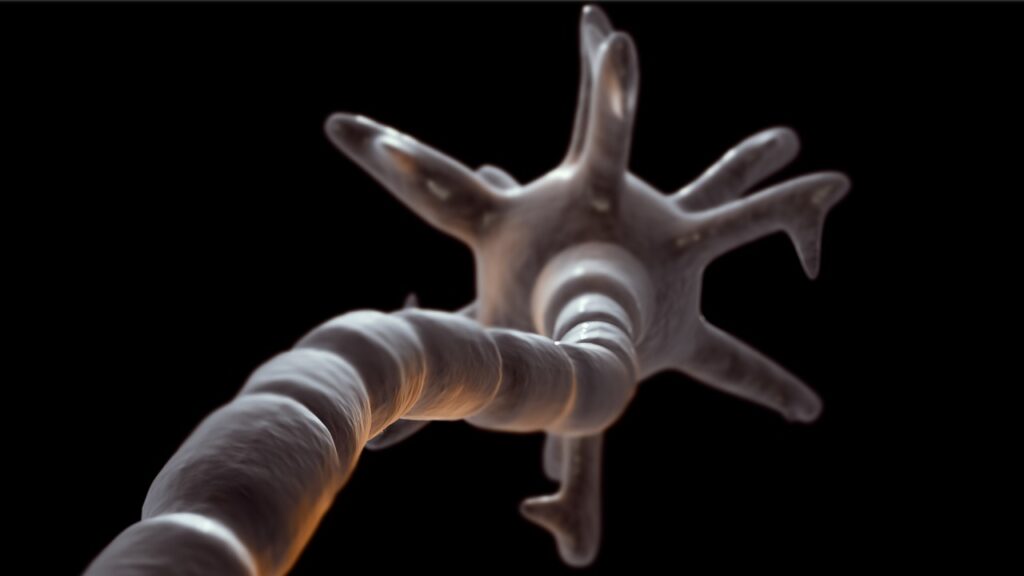

MSは、免疫システムが神経の「ミエリン鞘(myelin sheath)」という脂肪の保護層を誤って攻撃することにより発症します。

このミエリン鞘が破壊されると、脳と身体の間の情報伝達が遮断され、運動障害や感覚麻痺、さらには視力障害や記憶力・集中力の低下といった認知機能障害が発生するのです。